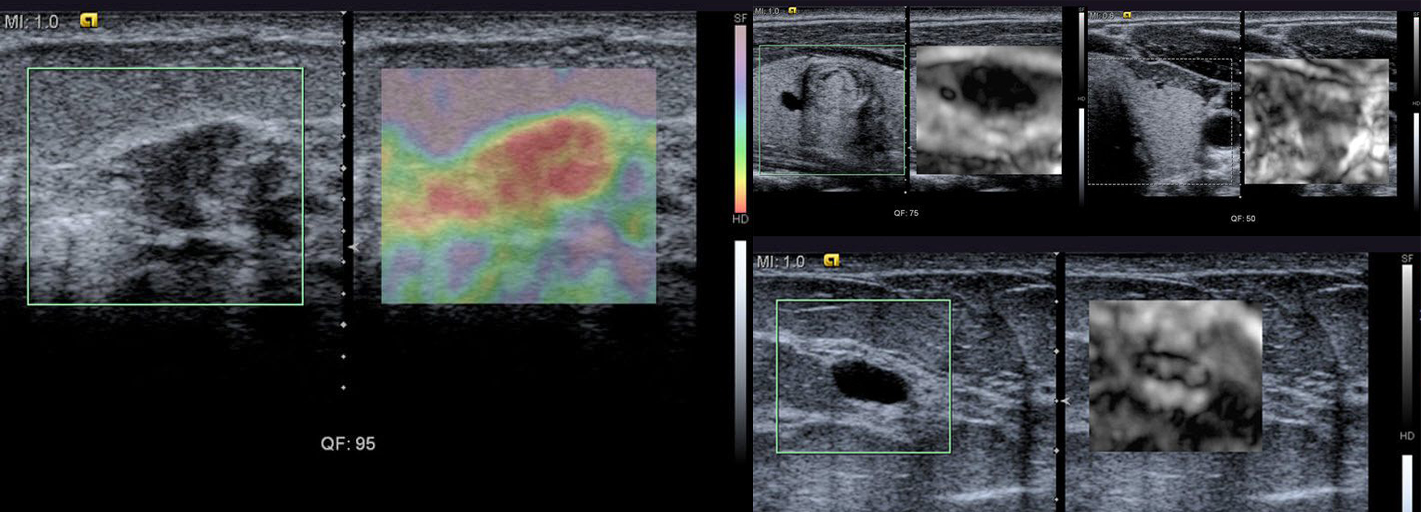

Ultrasonograf z elastografią Share Wave i kardiologią (CV Doppler)

SIEMENS ACUSON S3000

Ultrasonograf w pełni sprawny. Szczegółowo sprawdzony przez naszych techników, sprzedawany z aktualnym paszportem technicznym. Auto test sprzętu (oprogramowania w trybie serwisowym) nie wyświetla błędów i kończy się powodzeniem.

Aparat USG posiada dodatkowe oprogramowania:

- Aparat USG Siemens S3000 w pełni sprawny - używany, po przeglądzie technicznym, rok produkcji 2012/12 z elastografią oraz CV Dopplerem (kardiologia)